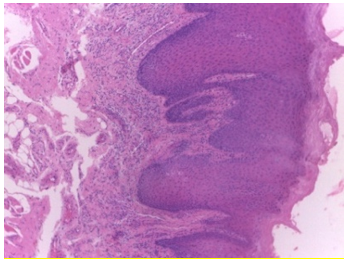

The efficiency of our research also depends on the dataset selected for implementation. The NDB-UFES dataset composed of histopathological images and patient data. The images are of different sizes with approximately 2048 × 1536 pixels. All total of 237 images in PNG format out of which 89 are leukoplakia with dysplasia, 57 are leukoplakia without dysplasia and 91 are OSCC images captured with an optical light microscope using 10x and 40x objective attached with a microscope camera. A hematoxylin-eosin stain is used in the histopathological slides from the biopsy of patients performed between 2010 and 2021 managed by Oral Diagnosis project of Federal University of Espírito Santo (NDB-UFES) [11]. The dataset contains sociodemographic data including age, gender and skin color as well as clinical data including alcohol consumption, sun exposure, tobacco use, lesion, type of biopsy, lesion surface and lesion color were also collected. The dataset has a separate patches folder consisting of 3736 patches of cancerous images as well.

This dataset also consists of patients’ clinical and demographic information in a CSV as well as XLS format. Representative sample images are shown in Figure 1, and a snapshot of the dataset obtained from Kaggle [36] is provided in Figure 2. Table 2 below provides the data dictionary of clinical data. The CSV file consists of a total of 237 records with 17 columns.

Figure 1. Sample images